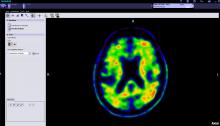

Cubresa Inc. recently announced the successful installation of their compact positron emission tomography (PET) scanner called NuPET for preclinical PET and magnetic resonance imaging (MRI) in the Department of Medical Imaging at the University of Arizona (UA).

Coronavirus (COVID-19) | May 11, 2021

Yael Eshet, M.D., MSc, a diagnostic radiology specialist at Sheba Medical Center in Israel, was the lead author on a recent study that showed COVID-19 (SARS-CoV-2) vaccine adenopathy can persist more than 6 weeks. This swelling of lymph nodes is similar to what is seen cancer and infections and the new findings show it can last longer than 7-10 weeks. The current recommended time people should delay medical imaging is 6 weeks after receiving a COVID vaccine to avoid a misdiagnosis,[2] but this new study shows there is increased inflammation shown on PET-CT imaging for much longer.

These were the findings in the Radiology published study "Prevalence of Increased FDG PET/CT Axillary Lymph Node Uptake Beyond 6 Weeks after mRNA COVID-19 Vaccination."[1]

Researchers using fluorodeoxyglucose (FDG)-positron emission tomography (PET) have found increased FDG uptake in the lymph nodes of patients 7-10 weeks past their second mRNA-based Pfizer-BioNTech COVID-19 vaccination. This new information indicates a persistent immune response that could be mistaken on imaging exams for serious conditions like lymphoma over a much longer period of time.

Recent recommendations for post-vaccine lymphadenopathy advise scheduling routine imaging, such as screening mammography, before, or at least 6 weeks after, the final vaccination dose to eliminate false positive results. However, this new research showed that avid axillary lymph node uptake was present beyond 6 weeks after the second vaccination in more than 29% of the patients in the study cohort.

The authors stated “This study shows that avid axillary lymph node uptake on FDG PET/CT can be detected in more than a quarter of our patient population even beyond 6 weeks after the second dose of the mRNA-based COVID-19 vaccination. Compared to a previous study showing normalization of FDG uptake within 40 days of receiving an inactivated H1N1 influenza vaccine, we found uptake persistence even at 70 days. Physicians should be aware of this potential pitfall.”

Some images in this video are from another Radiology study, which showed PET tracer uptake at the COVID vaccine injection site and other examples of axillary adenopathy.[3]

PET-CT | December 04, 2020

This is an example of Canon's Advanced intelligent Clear-IQ Engine (AiCE) AI-driven image reconstruction software that is now being used to improve image quality on the Canon Celesteion Prime PET/CT nuclear imaging system. The deep learning is used to enhance the iterative reconstruction used to reduce noise and sharped high contrast resolution on positron emission tomography (PET) images from the digital PET detector used on the system.

This example is a whole-body FGD PET scan of a patient with a large BMI with lung cancer.

The Cartesion Prime PET/CT is the industry’s only air-cooled digital PET/CT, provides variable bed time (vBT) acquisition as a standard feature. This and the new FDA 510(k)-pending AiCE technology were highlighted at the 2020 Radiological Society of North America (RSNA) virtual meeting.